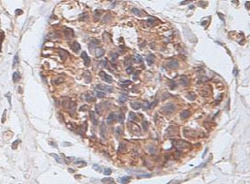

- Immunohistochemical staining of formalin-fixed paraffin-embedded human prostate carcinoma tissue showing cytoplasmic and membrane staining with PTP4A2 polyclonal antibody (Cat # PAB18892) at 1 : 100 dilution.

- Immunohistochemistry (Formalin/PFA-fixed paraffin-embedded sections)